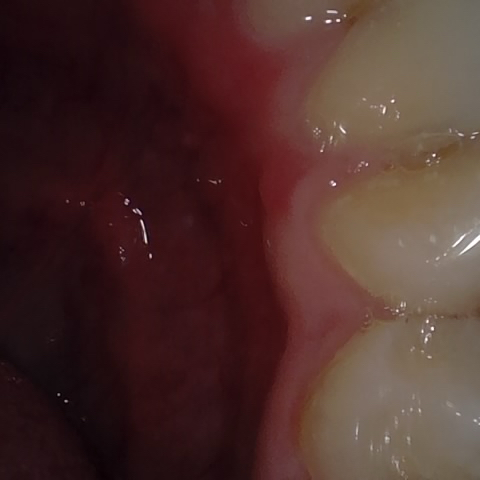

Annotated as "Good"